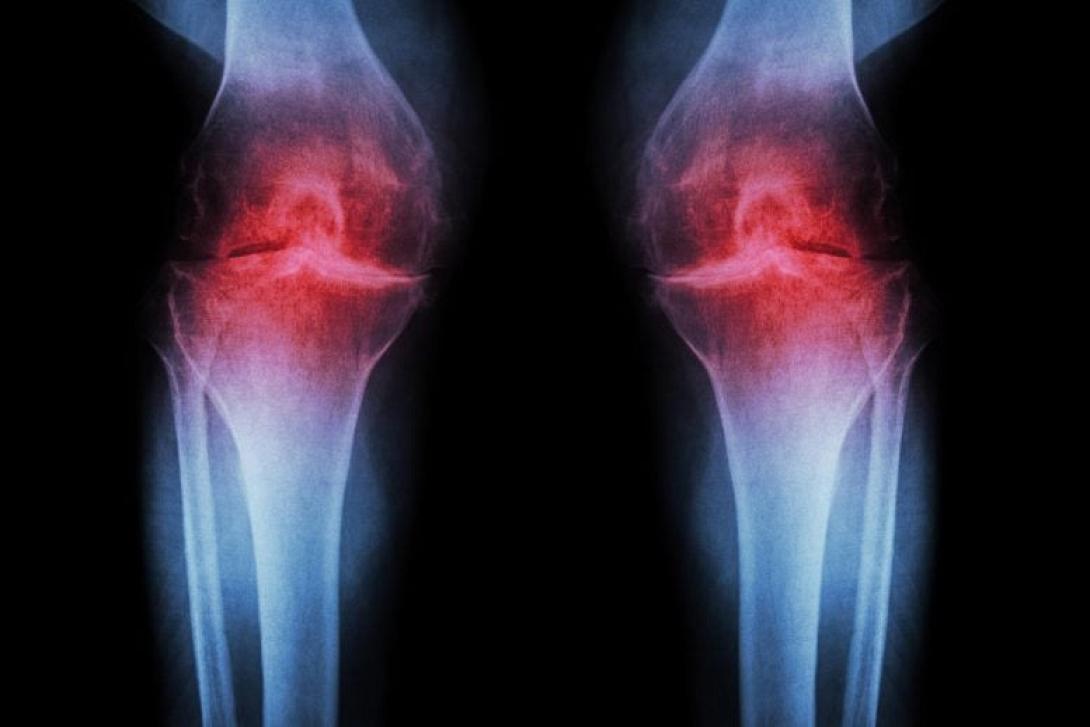

Ρευματοειδής αρθρίτιδα: Ξεκινά πολύ πριν εμφανιστούν τα συμπτώματα, διαπιστώνει μελέτη

Οι επιστήμονες της μελέτης διαπίστωσαν ότι η ρευματοειδής αρθρίτιδα (ΡΑ) δεν ξεκινά όταν εμφανίζεται ο πόνος, αλλά εξελίσσεται σιωπηλά επί χρόνια. Πρόκειται για μια σοβαρή αυτοάνοση ασθένεια που προκαλεί έντονη φλεγμονή και σταδιακή καταστροφή των αρθρώσεων. Τα νέα ευρήματα δείχνουν ότι άτομα με αυξημένο κίνδυνο για ΡΑ υφίστανται σημαντικές αλλαγές στο ανοσοποιητικό τους σύστημα πολύ πριν εκδηλωθούν τα συμπτώματα.